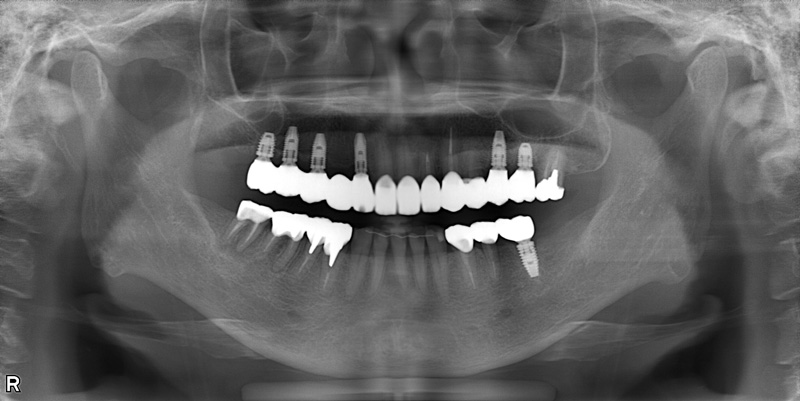

57歳男性

治療後

| 施術名 | インプラント治療 |

| 施術の説明 | インプラント治療とは、歯を抜いた所にチタン製の人工歯根を埋入し、新しく歯を入れる方法です。 |

| 施術の副作用 (リスク) | 腫れや疼痛を感じる、違和感を感じるなどの症状を生じることがあります。 |

| 施術の価格 | 53万円~+消費税 |